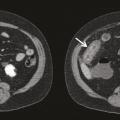

L’atteinte digestive est également fréquente et touche plus de la moitié des patients. Elle se manifeste généralement dans la semaine suivant l’apparition du purpura avec des douleurs abdominales épigastriques par atteinte duodénale, ou en regard de la fosse iliaque en cas d’iléite. Un saignement digestif peut survenir, chez 31 % des patients présentant une atteinte digestive, et être parfois gravissime, engageant le pronostic vital. Cependant, il est le plus souvent occulte ou sous forme de méléna. L’échographie ou le scanner peut être utile, montrant une paroi intestinale épaissie (fig. 3 ). La réalisation d’endoscopies digestive haute et basse permet d’objectiver un purpura muqueux, mais son intérêt est controversé du fait d’un risque de perforation digestive.